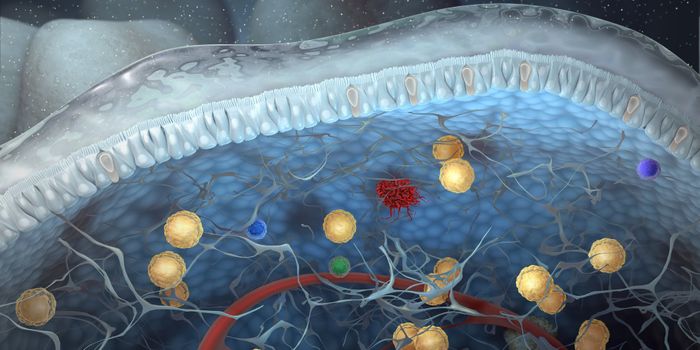

OCT 21, 2017VideosA new kind of treatment for some kinds of cancer has been in development for many years. Called CAR T-cell therapy, for ...